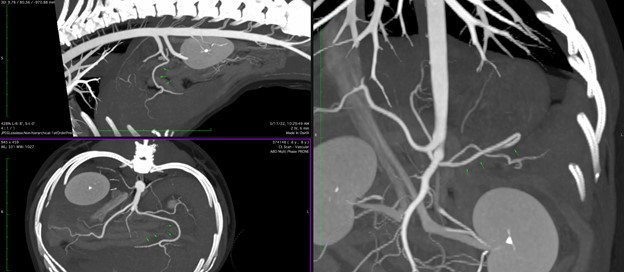

Figure 2: Computed tomography arterial angiogram demonstrating splenic artery branching off the celiac artery (arrows). Upper left image is the patient in sagittal with cranial to the left of the image and the celiac and cranial mesenteric artery can be seen branching off the abdominal aorta. The lower left image is the patient in axial with the common hepatic and splenic branches clearly visible. The right image is the patient in an oblique coronal view demonstrating all main branches off the celiac. All images are captured in a maximal-intensity projection to demonstrate arterial vasculature.